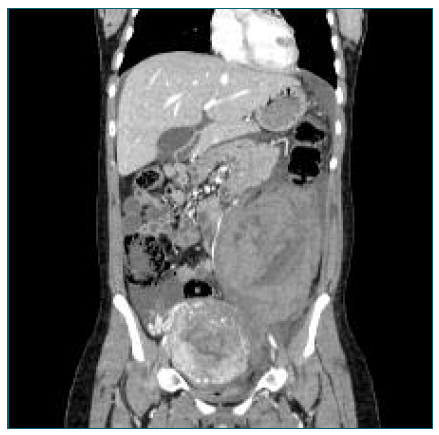

Initial laboratory tests revealed a hemoglobin drop from 11 g/dL in late pregnancy to 9.3 g/dL, suggesting mild postpartum anemia. A renal-bladder ultrasound and an abdominal X-ray imaging (Figure 1) were performed, excluding urinary and intestinal complications. Persistent pain along with an episode of lipothymia prompted an urgent abdominopelvic contrast-enhanced CT-scan, revealing a 19 cm retroperitoneal hematoma in the left flank and iliac fossa (Figure 2). Additionally, a 7 mm pseudoaneurysm in the LOA was identified as the source of intermittent hemorrhage (Figure 3A).

Figure 2 Abdominal-pelvic CT scan performed 2 days postpartum, showing a retroperitoneal hematoma measuring at least 12 × 13.4 × 19 cm (anteroposterior × transverse × longitudinal), localized in the left flank and iliac fossa. An enlarged uterus with a heterogeneous enhancement pattern results from normal postpartum changes.